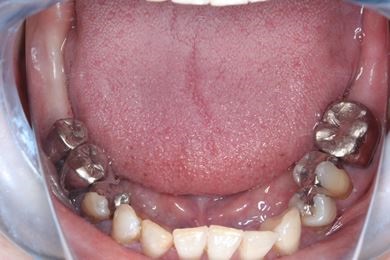

インプラント治療+セラミック治療

| 治療内容 | インプラント3本、ジルコニアフレームオールセラミッククラウン7本(ジルコニア用土台1本)、メタルボンドセラミッククラウン3本(メタルボンド用土台3本)、ハイブリッドセラミッククラウン3本、ハイブリッドセラミックインレー3本 | ||||||||||||||||||||||||||||||||